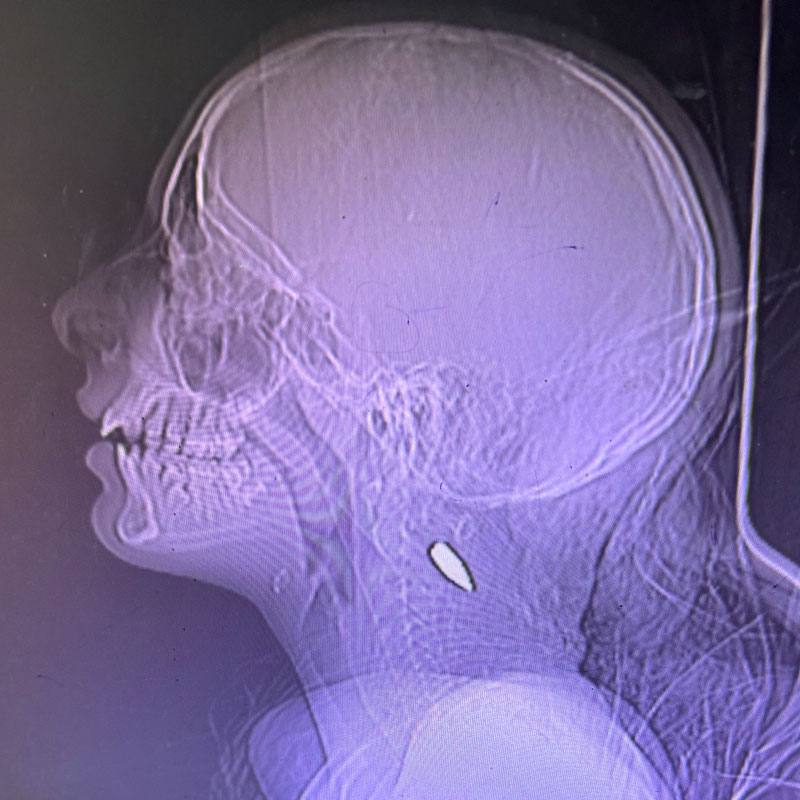

شهادت بیشماری از پزشکان در مورد تیراندازی مداوم نیروهای اسرائیلی به سر کودکان فلسطینی در نیویورک تایمز وجود دارد. این گزارش با عنوان «65 پزشک، پرستار و پیراپزشک: آنچه در غزه دیدیم» اینطور شروع میشود: "من از 25 مارس تا 8 آوریل به عنوان جراح تروما در غزه کار کردم. در اوکراین و مناطق درگیری داوطلب بودم، خشونت بسیار دیدم؛ اما بسیاری چیزها در بیمارستان غزه برجسته بود، تقریباً هر روز که آنجا بودم، یک کودک خردسال جدید را می دیدم که از ناحیه سر یا قفسه سینه مورد اصابت گلوله قرار گرفته بود و تقریباً همه آنها فوت شدند. آن زمان، تصور میکردم که این باید کار یک سرباز سادیستی باشد که در همان نزدیکی قرار دارد. اما پس از بازگشت به خانه، با یک پزشک فوریتهای پزشکی آشنا شدم که دو ماه قبل از من در بیمارستان دیگری در غزه کار میکرد. به او گفتم: « نمیتوانستم تعداد بچههایی را که به سرشان شلیک شده است، باور کنم. در کمال تعجب، او هم پاسخ داد: بله، من هم همینطور. هر روز.» این عکسهای اشعه ایکس توسط دکتر میمی سید، که از 8 اوت تا 5 سپتامبر در خان یونس کار میکرد، ارائه شده است. سر یا سمت چپ قفسه سینه، معمولاً اینها تک شات بود. بیماران یا مرده یا با حال وخیم وارد شدند و اندکی پس از رسیدن جان خود را از دست دادند.